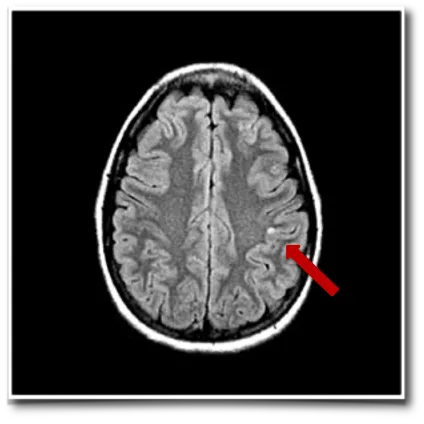

琳娜的MRI检查显示顶叶区域存在小型囊性病变,该病灶被确认为癫痫频繁发作的责任病灶。脑磁图进一步在管理躯体感觉的中央后回区域监测到异常癫痫样放电。下图分别显示矢状位(左)和轴位(右)Rolandic区(中央区)棘波簇(黄色点带橙色轮廓)。